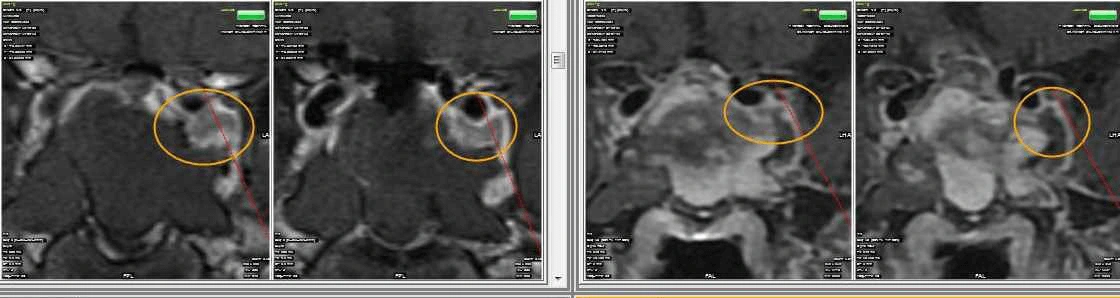

• الرنين المغناطيسي للدماغ مع تركيز خاص على الغدة النخامية.

• فحص قاع الجمجمة لتحديد مدى انتشار الورم.

• تشخيص دقيق لحالات أورام الغدة النخامية باستخدام أحدث أجهزة الرنين المغناطيسي.